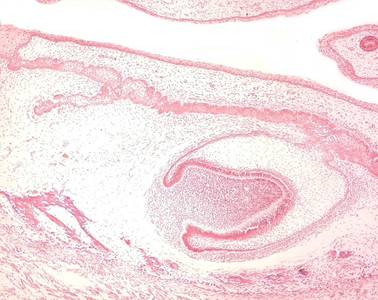

Präparat 45: Zahnanlage, H.-E.

Zahnleiste

erstes Stadium der Zahnanlage in Form von bogenförmigen Absenkungen des Epithels der Mundbucht im Bereich des späteren Ober- und Unterkiefers. An ihrem Ende entwickelt sich die Zahnknospe, aus der das Schmelzorgan hervorgeht.

Zahnsäckchen

Verdichtung des Mesenchyms, das die Zahnanlage umgibt. Aus ihm entwickeln sich die Bestandteile des Zahnhalteapparates.

Es handelt sich um einen Schnitt durch die herausgelöste Maxillar- und Mandibularregion eines menschlichen Embryos. Das Präparat hat also präparationsbedingte künstliche Schnittflächen und zwei natürliche, von Epithelien überzogene Oberflächen: die Haut auf der Außenseite und die Schleimhaut im Innern der Mundhöhle. Die Wangenhaut ist beim Embryo noch nicht so dick und deutlich verhornt wie beim Erwachsenen, läßt sich aber anhand der zahlreichen vom Epithel in die Tiefe eingestülpten Haarfollikel identifizieren. Die stark gebuchtete Mundhöhle (in der u.U. auch die Zunge angeschnitten ist) trägt ein typisches mehrschichtiges unverhorntes Plattenepithel. Schon in der Übersicht erkennt man, daß von diesem Epithel ausgehend im Ober- und im Unterkieferbereich schlauchartige, manchmal gewundene Gebilde (die Zahnleisten) sich in die Tiefe senken, die in epithelialen Verdichtungen, den Zahnknospen der Zahnanlagen enden. Im hier gezeigten Entwicklungsstadium hat sich die Zahnknospe bereits zur Zahnglocke, dem Schmelzorgan, differenziert. Im Inneren der Glocke liegt die Zahnpapille aus verdichtetem Mesenchym. Außen um die Zahnglocke verdichtet sich das Mesenchym zum Zahnsäckchen.